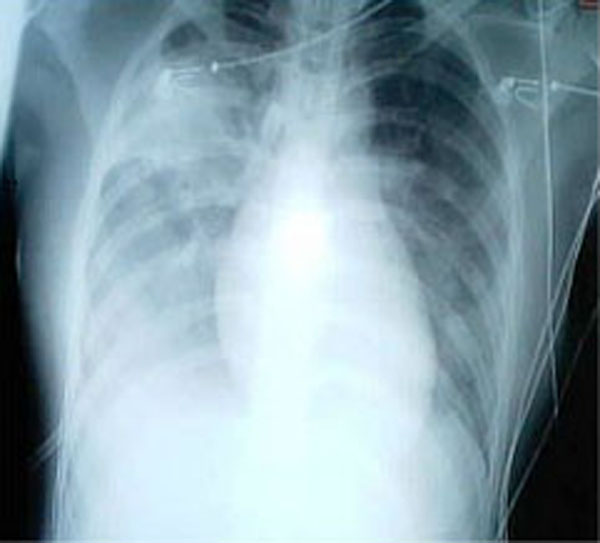

Most healthy people fight off the virus within 7 – 10 days. Those who do not become more seriously ill because the immune system overreacts and this leads to pneumonia, a condition in which the alveoli fill with water as a result of excess inflammation and tissue damage. This may be caused by coronavirus binding to ACE2 on type-2 pneumocytes and other membranes. ACE2 regulates a protein called angiotensin II, which raises blood pressure and causes inflammation. When coronavirus binds to ACE2, it inhibits its ability to regulate angiotensin II, thus the overreaction.

This can lead to acute respiratory distress syndrome, which happens when the inflammation of the lungs is so severe the body cannot get enough oxygen to survive, and can lead to organ failure. At this point a person is at risk of death and is admitted to intensive care and put on a ventilator.